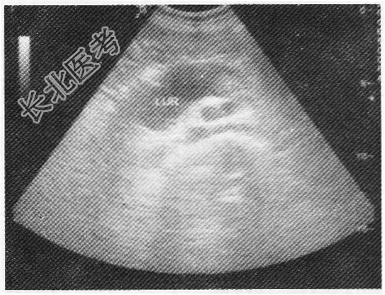

- 单项选择题男性,60岁, 无痛性血尿伴左侧腰部疼痛不适1月余;超声检查左肾集合系统分离3.7cm, 左输尿管如图所示最可能的诊断为

A、左输尿管结石

B、左输尿管癌

C、左输尿管狭窄

D、左输尿管畸形

E、左输尿管炎症